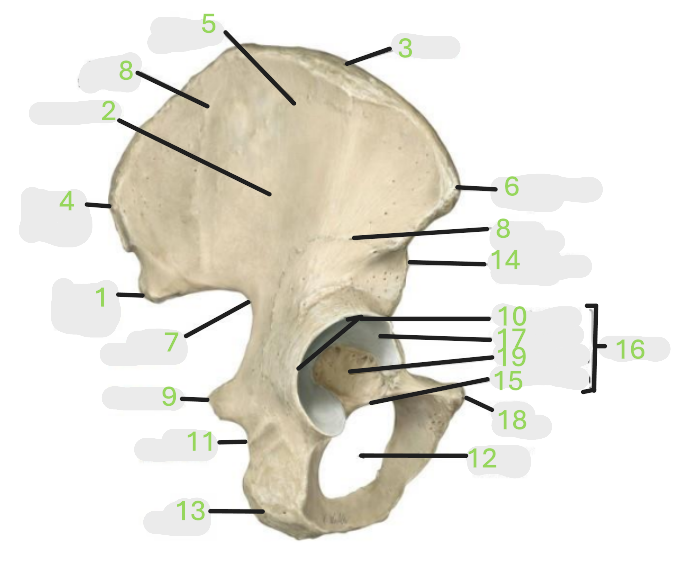

Where is the posterior inferior iliac spine

1

Where is the gluteal surface

2

Where is the iliac crest

3

Where is the posterior superior iliac spine

4

Where is the anterior gluteal line

5

Where is the anterior superior iliac spine

6

Where is the greater sciatic notch

7

Where is the inferior gluteal line

8

Where is the ischial spine

9

Where is the acetabular rim

10

Where is the lesser sciatic notch

11

Where is the obturator foramen

12

Where is the ischial tuberosity

13

Where is the anterior inferior iliac spine

14

Where is the acetabular notch

15

Where is the acetabulum

16

Where is the lunate surface

17

Where is the pubic tubercle

18

Where is the acetabular fossa

19